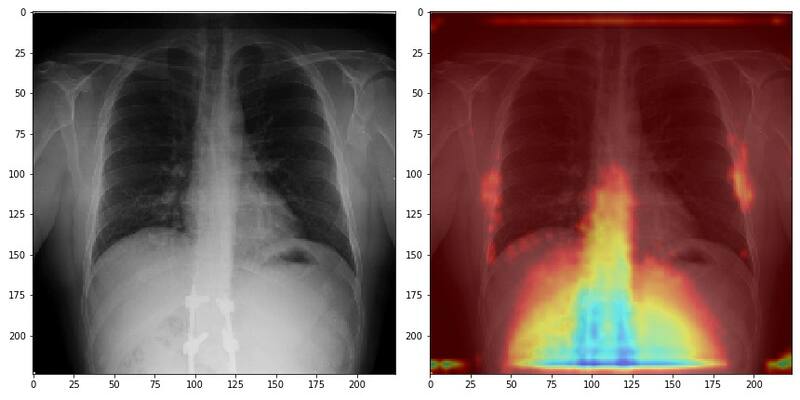

Se llama Berta. Es el nombre de la perra de Manuel Torres, líder de Ingeniería de Google Cloud para Chile y, por lo mismo, fue el nombre elegido para la “máquina” que constituye el centro del proyecto que ha encabezado en los últimos cuatro meses: un sistema de inteligencia artificial que, aprendiendo de miles de radiografías de tórax, es capaz de detectar la presencia de Covid 19 en una persona incluso antes de que presente síntomas.

De modo que, de cierta manera, poner todo esto al servicio del screening de posibles casos de Covid19 tenía sentido. De hecho, ya existía un recurso para ello. El doctor Mijac comenta que existe una base de datos gratuita online con miles de radiografías de pacientes con Covid 19, principalmente italianos. “Las usamos en un principio”, comenta. Fueron las primeras lecciones de Berta. “Pero llegamos a un punto donde vimos que no era de la calidad que queríamos; además eran de definición muy dispareja”. La decisión fue entonces comenzar a reemplazar ese banco de imágenes con radiografías de pacientes chilenos. Hoy, la totalidad de imágenes con las que opera el sistema son locales. Eso les permitió además clasificar y controlar mejor la toma de las muestras y clasificarlas.

“Y otro grupo está compuesto por 500 imágenes, que acabamos de terminar de recolectar, que son pacientes que consultan en nuestros centros médicos o clínicas con patologías respiratorios y a los que se decide tomarle una PCR”, explica Mijac. “A estos pacientes les ofrecemos en ese momento en forma gratuita tomarle una radiografía de tórax. Luego esperamos los resultados de la PCR. Cuando ése test es positivo, marcamos esa radiografía (y en ese momento se desmarca del individuo, para protección de su privacidad) y ese es el grupo que nos sirve para indicarle a la Inteligencia artificial cómo se ve el Covid 19 en una radiografía”.

En sus más de dos décadas observando radiografías, el doctor Mijac dice que no se podría imaginar tener esa capacidad de observación. “No es un problema de conocimientos, sino de capacidad del ojo. Le pedimos a la inteligencia artificial que nos preste su ojo biónico”.